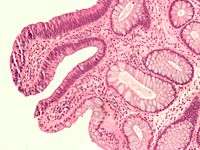

Traditional serrated adenoma. H&E stain.